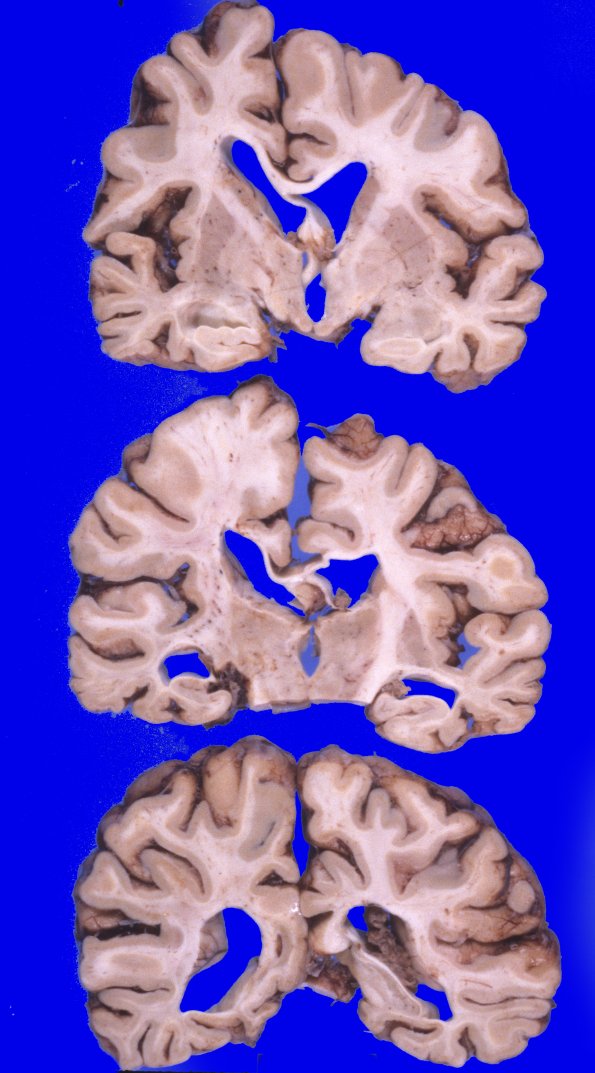

Coronal sections confirm the degree of diffuse cortical atrophy with narrow gyri and wide sulci with a large amount of ventricular dilatation and blunting. The cerebral white matter is diffusely firm to palpation. The corpus callosum is extremely thin.